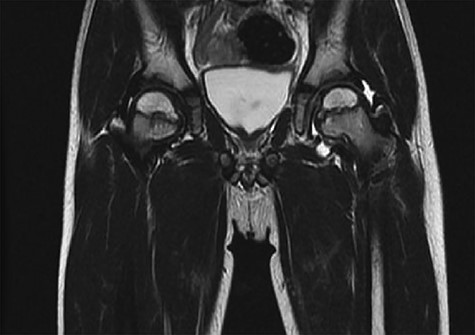

CT hips reported a well-defined lesion seen bilaterally in the neck of femur anterior infero-medial aspect, more prominent on the left side measuring 7 x 3 mm on left side both in coronal (Fig. 3) and axial (Fig. 4) views. On the right side, other lesion measuring 2 x 1 mm (Fig. 5) seen in coronal view. These two lesions are well defined with a sclerotic border with a small cortical defect. The lesion shows fat density. The symmetrical appearance of the lesion combined with the fat density and location suggest the diagnosis of synovial herniation pit. MRI Pelvis revealed minimal left hip joint effusion with loculated fluid seen along the trochanteric bursa with the largest measuring 0.9 x 1.5 cm (Fig. 6, 7).

Sowed coronal cut of CT hips demonstrating the synovial pit on left and right side.